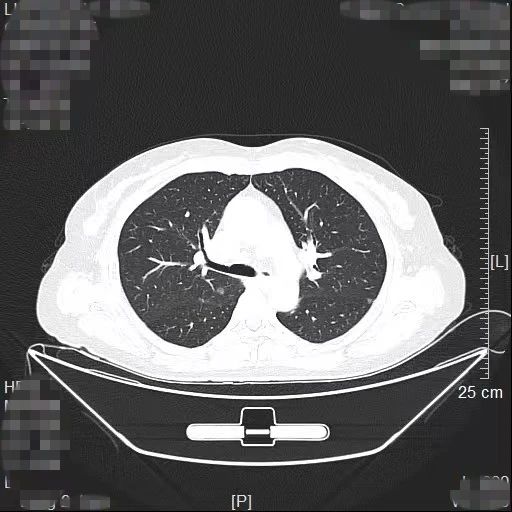

患者林女士今年65岁,长期旅居国外的她在回国后常规体检时查出右肺有2个高危的磨玻璃结节,慕名找到我院胸部肿瘤外科方卫民主任医师。医生团队详细分析了患者的肺部CT及三维重建结果,发现2个结节分别位于右上肺后段边缘及右中肺叶中央,如果直接采用手术切除的方法,要多切除整个右肺中叶,将损失较多的正常肺组织,影响生活质量,得不偿失。

由于患者签证时间将到,无法分次手术,医生团队经过反复讨论,最终为患者量身定做了“针孔消融+单孔微创”的杂交手术方案。首先在医院肿瘤与血管微创介入治疗中心CT引导下为患者右中肺叶结节进行热消融治疗,仅仅一个针眼;接着进行单孔胸腔镜亚肺段切除,仅仅一个3cm大小的切口,术中冰冻病理报告:原位腺癌,疑有浸润。顺利为患者解除了肺部的2个健康隐患。